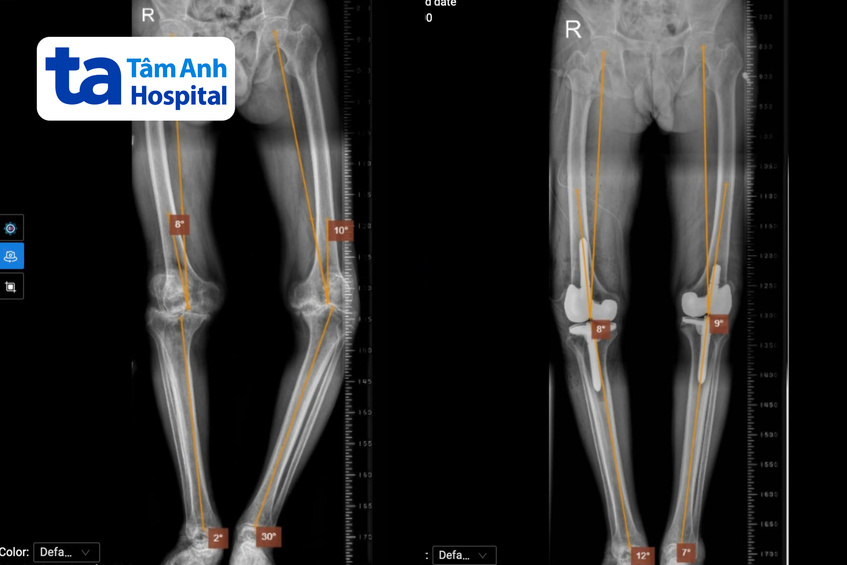

Ông Tri từng phẫu thuật tái tạo dây chằng chéo trước ở chân trái hơn 10 năm trước. Tuy nhiên sau đó, khớp gối không ổn định, hai chân cong vẹo về một phía khiến ông không thể đi lại bình thường, di chuyển khó khăn và phải có người hỗ trợ. Kết quả chụp X-quang tại Bệnh viện Đa khoa Tâm Anh TP HCM cho thấy ông Tri bị thoái hóa khớp gối nặng ở cả hai chân, chân trái vẹo trong hơn 30 độ và chân phải vẹo ngoài hơn 10 độ. Tình trạng bệnh kéo dài làm sụn khớp gần như không còn, khiến các đầu xương bị cọ xát, gây mất xương, co rút dây chằng trong và làm thay đổi trục khớp gối, dẫn đến biến dạng chân.